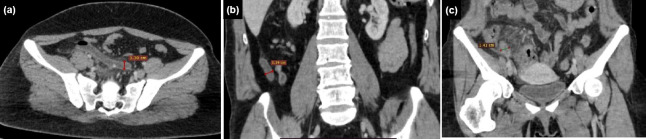

Methods: Between January 2020 and January 2023, 294 patients diagnosed with AA were retrospectively analyzed. Of these, 140 (47.6%) had appendicoliths (Group 1), and 154 (52.4%) did not (Group 2). CT findings of AA and CTAS were evaluated. CBC parameters, CRP levels, and SII scores were compared between the groups, and the presence of appendix perforation was analyzed.

Results: The mean diameter and wall thickness of the appendix, presence of intra-abdominal fluid, and severity of periappendi-ceal fat stranding were higher in Group 1 (p<0.001, p=0.024, p=0.009, p<0.001, respectively). The CTAS was also higher in Group 1 (7.51±2.35) compared to Group 2 (6.38±2.41; p<0.001). There was a positive correlation between the diameter of the appendicolith and CTAS (rho=0.450, p<0.001). In Group 1, CTAS was higher in patients with more than one appendicolith (p=0.003). Perforation was observed in 15 patients (10.7%) in Group 1 and five patients (3.2%) in Group 2, with a higher incidence in Group 1 (p=0.011). Among Group 1 patients, the perforation rate was higher in those with more than one appendicolith (p=0.019). The mean CTAS was higher in patients with appendiceal perforation (10±1.13) compared to those without perforation (7.22±2.29) (p<0.001). Monocyte (MONO) counts were also higher in Group 1 (p=0.002). Other CBC parameters, CRP levels, and SII scores did not differ significantly between Groups 1 and 2 (p>0.05). However, CRP levels and MONO counts were elevated in patients with perforated appendicitis (p<0.001 and p=0.026, respectively).

Conclusion: Acute appendicitis with appendicoliths is associated with more pronounced inflammation and a higher rate of perforation. CTAS, CRP, and MONO levels tended to be elevated in cases of appendiceal perforation. A comprehensive evaluation incorporating the presence of appendicoliths, CTAS, and laboratory parameters may provide valuable insights into the severity of inflammation in AA.